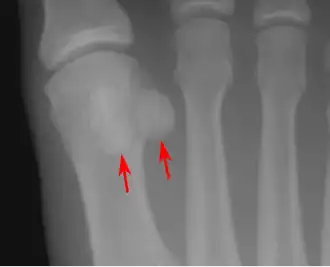

- One or both of the sesamoid bones under the first metatarsophalangeal joint (of the great toe) can be multipartite – in two or three parts (mostly bipartite – in two parts).[12]

Lateral view.[11] -

Bipartite medial sesamoid bone under the first metatarsophalangeal joint of the great toe of the left foot of an adult woman.